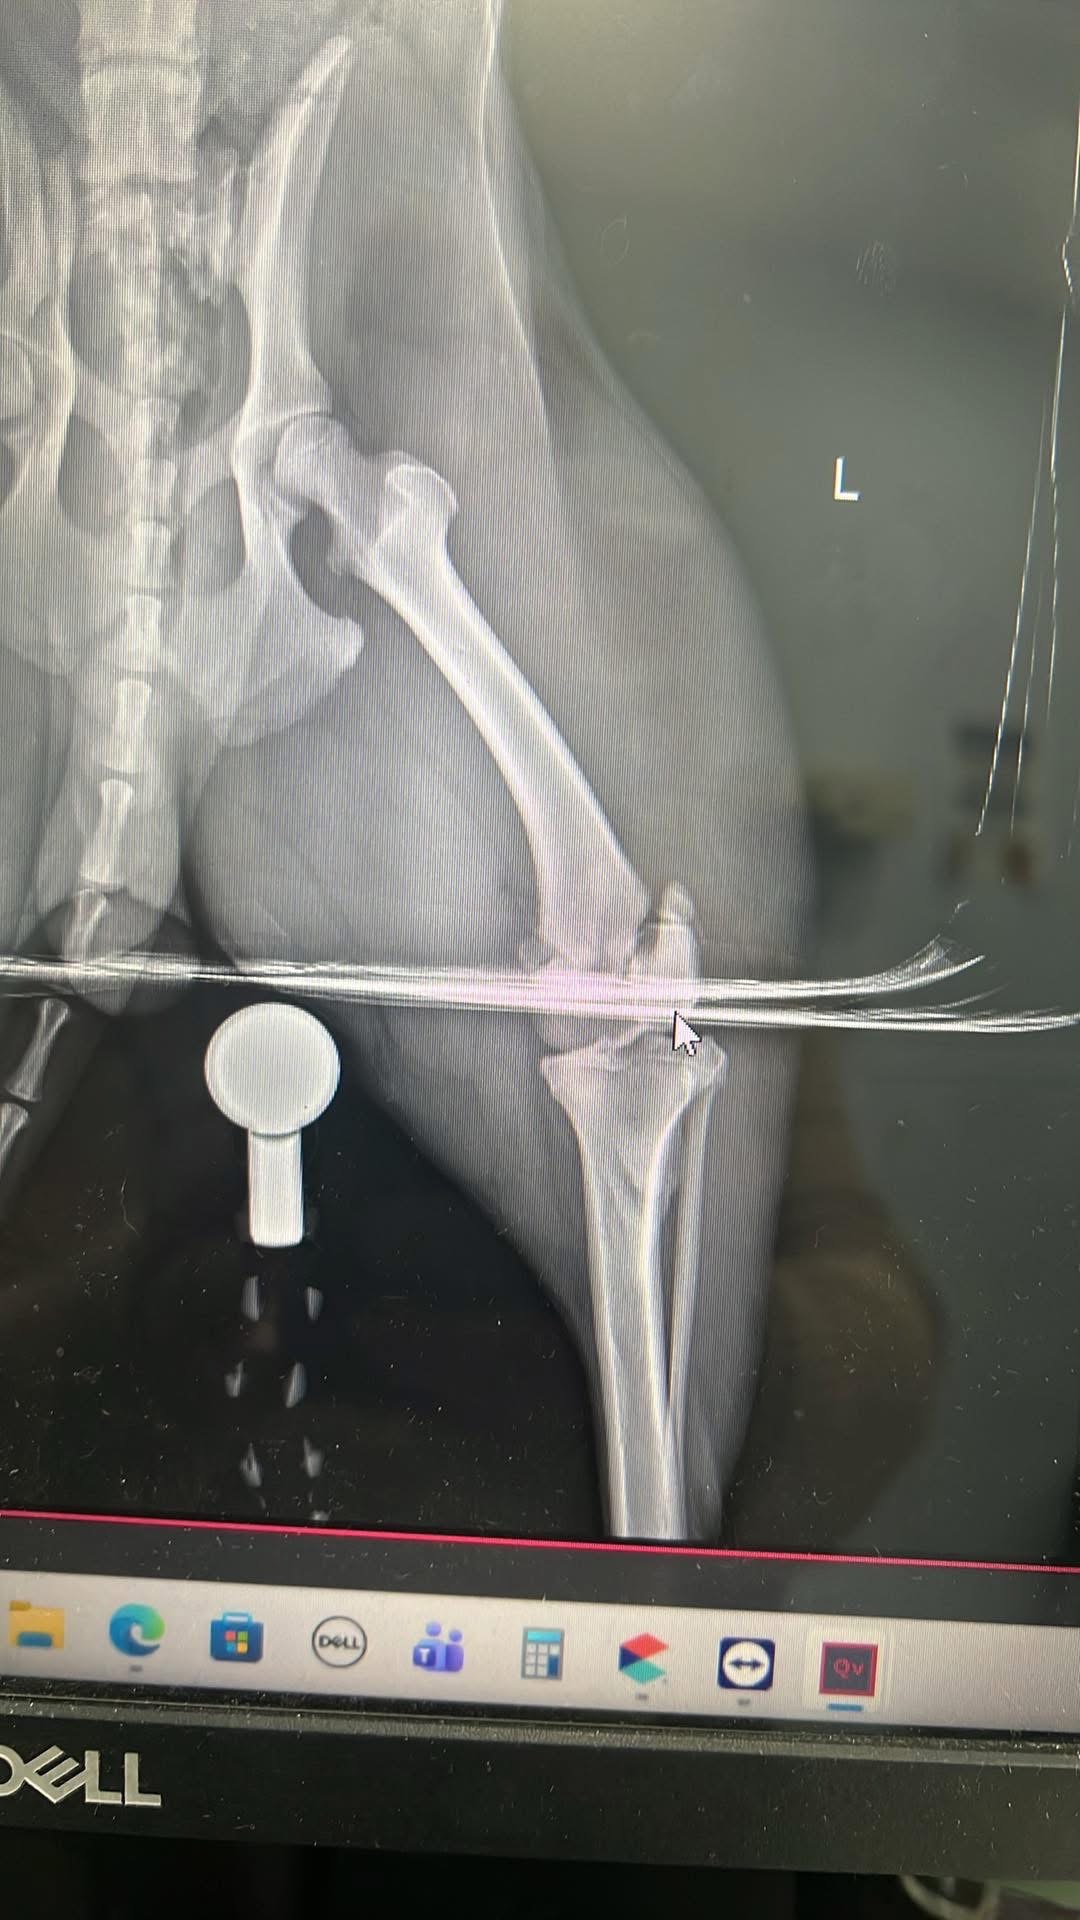

Toby has been with us since the day he was born, and he’s truly the sweetest, most gentle dog I’ve ever known. He’s a big part of our family, always bringing us joy and comfort. Recently, Toby managed to escape and was tragically hit by a car. The accident left him unable to walk, with a broken hip and two broken back legs. Watching him try his best to get up and move, despite the pain, is heartbreaking. He’s fighting so hard, and it’s clear he wants nothing more than to be back on his feet, playing and cuddling with us again.

Toby’s only chance at recovery is emergency surgery. Without it, he won’t be able to walk or enjoy the life he loves. The cost of the surgery is overwhelming for us, and we can’t imagine losing him when he’s trying so hard to stay strong. We’re reaching out to our community for help because we believe in the kindness of others and the power of coming together in tough times.

Toby’s only chance at recovery is emergency surgery. Without it, he won’t be able to walk or enjoy the life he loves. The cost of the surgery is overwhelming for us, and we can’t imagine losing him when he’s trying so hard to stay strong. We’re reaching out to our community for help because we believe in the kindness of others and the power of coming together in tough times.